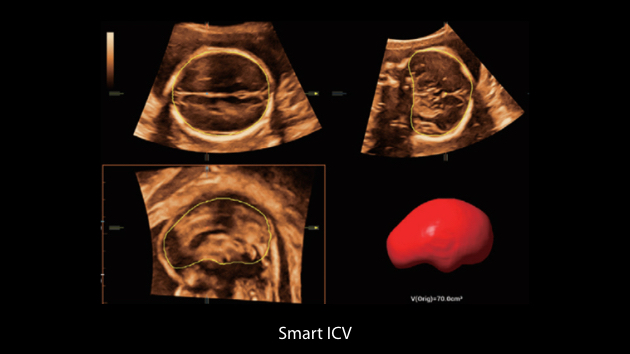

De Nuewa I9, speciaal ontworpen voor vrouwen en neonatale gezondheidszorg, biedt een innovatieve ervaring van binnenuit. Deze innovaties zijn ontwikkeld op basis van diepgaande inzichten in complexe klinische scenario's en bieden nauwkeurige en tijdige antwoorden, evenals een uitstekende effici?ntie en opmerkelijke gebruikerservaring.